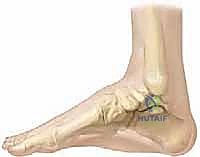

لفهم طبيعة العلاج، يجب أولاً فهم التعقيد التشريحي للقدم الحنفاء. لا يقتصر التشوه على عظمة واحدة، بل يشمل شبكة من العظام، الأربطة، والأوتار. يختصر أطباء العظام هذا التشوه بكلمة (CAVE)، والتي تمثل أربعة تشوهات متداخلة:

- التجويف (Cavus): ارتفاع غير طبيعي في قوس القدم الداخلي نتيجة قصر انقباضي في العضلات الداخلية للقدم.

- التقريب (Adductus): انحراف مشط القدم والأصابع نحو الداخل (باتجاه خط الوسط للجسم).

- الانقلاب الداخلي (Varus): ميلان عظمة العقب (الكعب) نحو الداخل، مما يجعل باطن القدم يواجه القدم الأخرى.

- الانثناء الأخمصي (Equinus): شد شديد في وتر أخيل (العرقوب) يجعل القدم موجهة للأسفل، مما يمنع الطفل من وضع كعبه على الأرض.